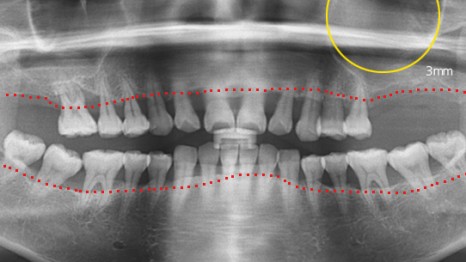

치조골 손실이 심한 상태에서의 치료 사례

염증으로 인해 치조골 손실이 많은 상태였으나,

치주 치료를 통해 잇몸 건강이 회복되었고,

앞니는 발치 대신 크라운으로 수복할 수 있었습니다.

타 병원에서는 총 12개의 임플란트 식립이

필요하다는 진단을 받으셨지만,

본원의 치주치료를 통해 잇몸 상태가 개선되었고,

발치를 피할 수 있었습니다.

파노라마 촬영 결과, 초기 염증으로 인

치조골 손실이 심각했던 상황에서, 치주 치료 후

앞니의 건강 상태가 개선된 점이 확인되었습니다.